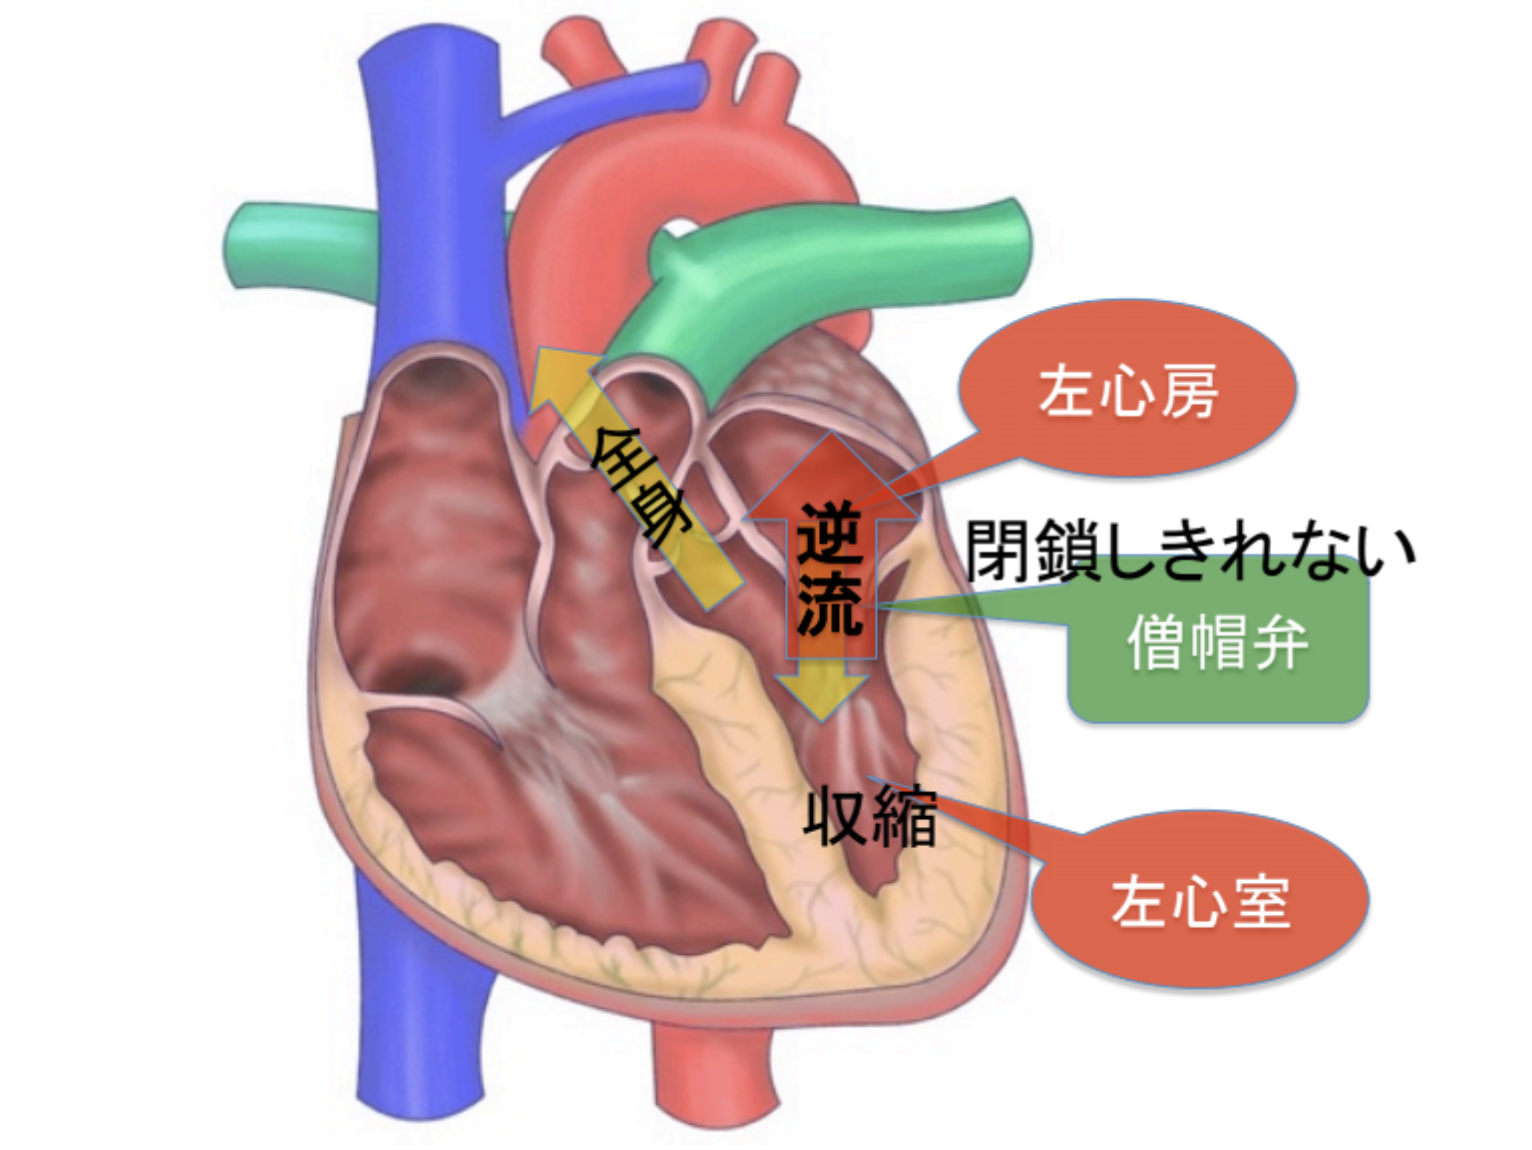

12月より新しく「動物医療センター目黒中央」が開院いたしました。 64列CT画像検査の設備が備わっております。今まで目白で撮影を行っていましたが、距離が近くなったことで利便性が良くなりました。 CT画像検査でお悩みの方はご相談くださいませ。 また循環器認定医の獣医師が診察していますので、循環器診察も得意としております。腹腔鏡も可能となりますのでご相談ください。 住所:東京都目黒区鷹番1-1-20 電話番号:03-6412-8303 詳細はホームページをご覧ください